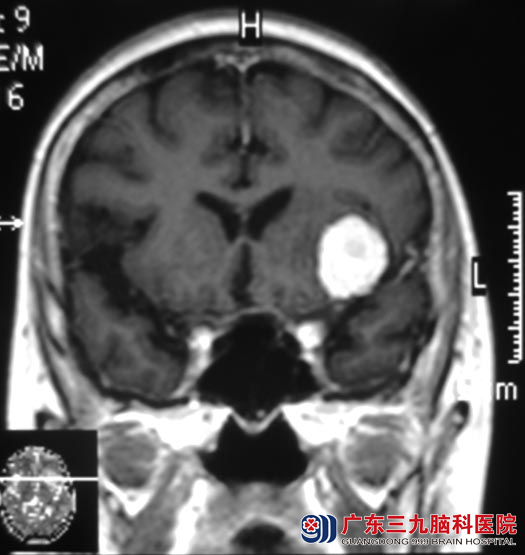

王奶奶今年76岁,一个月前开始出现头痛,以双侧额颞部明显,呈阵发性钝痛,偶有头晕。在当地医院行头颅CT检查,结果提示:左额叶占位,考虑肿瘤性病变,医生告知他们需要手术治疗。广东三九脑科医院头颅MR检查提示病变大小约21.6mm×23.6mm×23.8mm,考虑脑膜瘤。

心脏彩超检查提示:主动脉瓣退行性变并轻度返流,左室扩大;左室顺应性下降,经心内科专家会诊后,认为可以耐受手术。8月20日,由综合神经外科 鲁明主任主刀,在全麻下行左侧蝶骨嵴脑膜瘤切除术,术中见肿瘤基地部位于左侧蝶骨嵴,呈灰白色,质软,血供一般,与硬膜粘连紧密,予显微镜下小心分离,分块予肿瘤全切,手术顺利。经过一段时间的治疗,王奶奶没有出现任何并发症,顺利康复。病理结果为:脑膜皮细胞型脑膜瘤(WHO I级)。